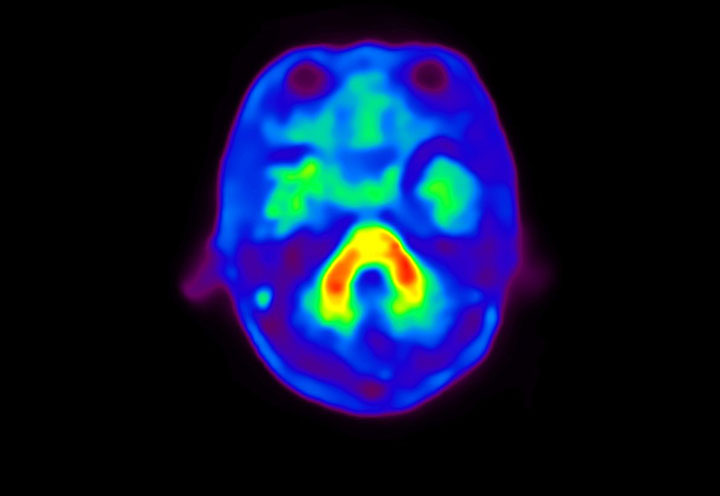

Head / Case4 : Amyloid

Sagittal

Courtesy : Kindai University Hospital

- Injected dose: 3.21 MBq/kg, 18F-Flutemetamol

- Uptake time: 100 minutes

- Scan time: 20 minutes